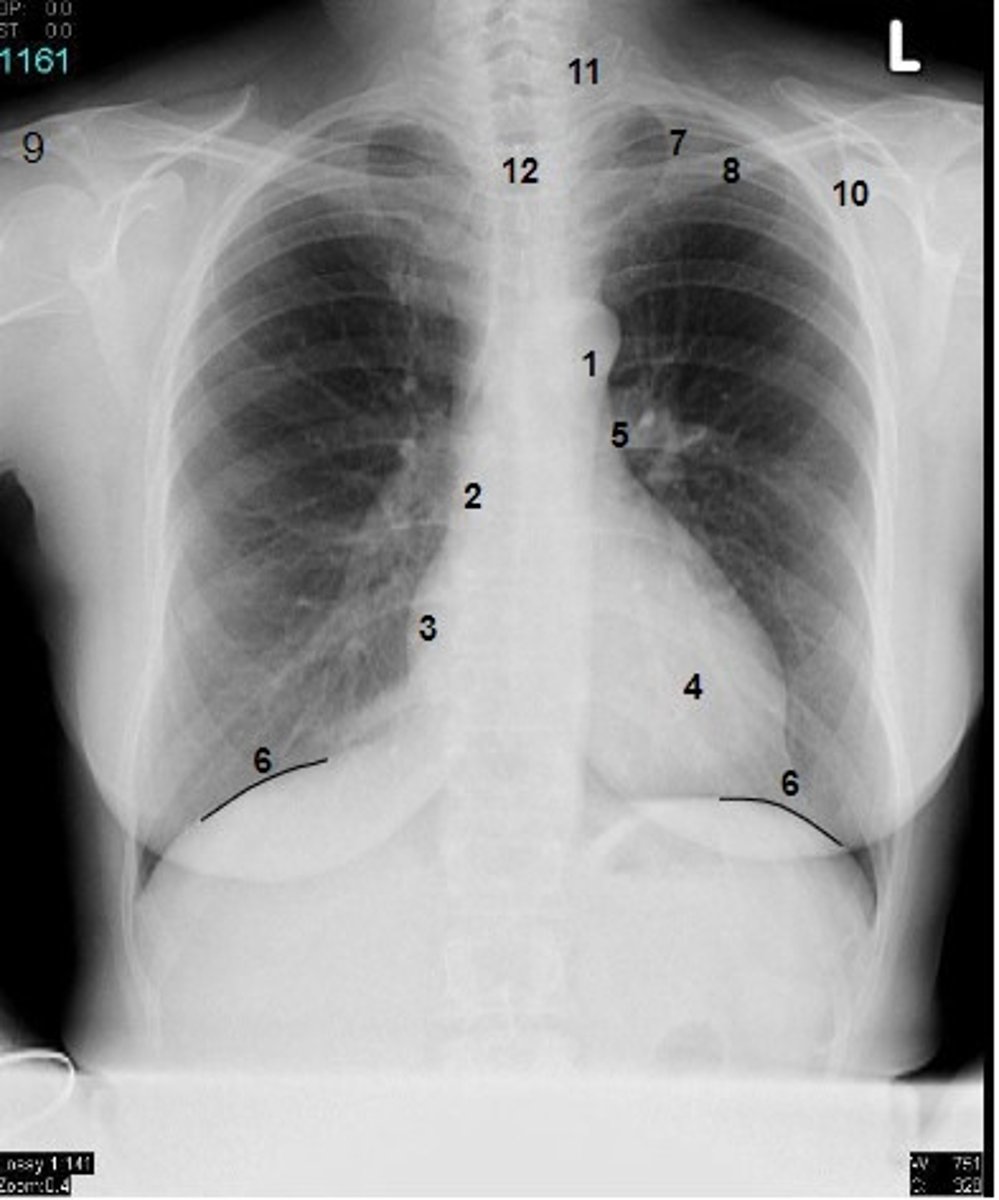

1

at what number is the arch of aorta?

2

at what number is the superior vena cava

3

at what number is the right atrium

4

at what number is the left ventricle

5

at what number is the primary bronchus

6

at what number is the dome of diaphragm

7

at what number is the first rib

8

at what number is the clavicle

9

at what number is the acromion of scapula

10

at what number is the coracoid process of scapula

11

at what number is the transverse process of vertebra

12

at what number is the spinous process of vertebra